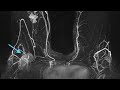

Симптомы рака легких на ранней стадии у мужчин и женщин первые признаки могут быть различными и не всегда однозначными. В ранней стадии рак легких часто не проявляет явных симптомов, что затрудняет его своевременное обнаружение.